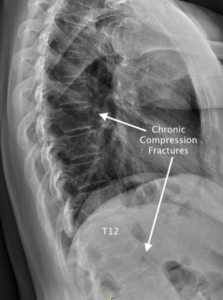

1) For the chiropractor to learn the most common causes, locations, and hallmark x-ray findings of compression fractures and spondylolysis.

I. Imaging of Compression Fractures